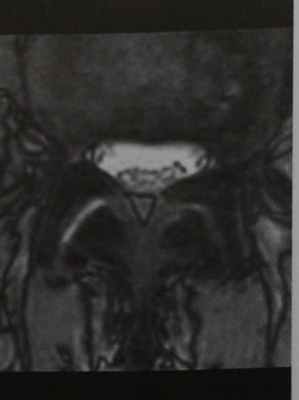

На ЭЭГ при конвекситальном арахноидите обнаруживаются локальные изменения биопотенциалов, а у больных с эпилептическими припадками – типичные для эпилепсии изменения. Решающее значение в диагностике арахноидита имеют данные томографии головного мозга (КТ и МРТ), свидетельствующие о расширении субарахноидального пространства, желудочков и цистерн мозга, иногда кисты в подоболочечном пространстве, при отсутствии очаговых изменений в веществе мозга. КТ и МРТ головного мозга позволяют выявить морфологические изменения, которые сопровождают арахноидит (спаечный процесс, наличие кист, атрофические изменения), определить характер и степень гидроцефалии, исключить объемные процессы (гематому, опухоль, абсцесс головного мозга). Изменения формы подпаутинных пространств могут быть выявлены в ходе КТ-цистернографии.

Целью исследования явилось определение особенностей МРТ исследований у детей с кистозным арахноидитом с симптоматической эпилепсией.

Материалы и методы: МРТ исследования были проведены среди 20 детей с кистозными арахноидитами осложненными симптоматической эпилепсией. Возраст детей варьировал от 3 года до 14 лет. Дебют эпилептических приступов отмечался с момента рождения до 13 лет, средний возраст дебюта 4,2±0,96 лет. Длительность заболевания в среднем составила 3,2±0,47 лет. МРТ исследования проводили по стандартной технологии (аксиальный, фронтальный и сагиттальный проекции). Применялись следующие стандартные программные режимы:

Результаты исследования. При обследовании 18 детей с кистозным арахноидитом осложненным симптоматической эпилепсией у 1 (5,5 %) случай установлено смещение срединных структур головного мозга, у 3 (16,7 %) детей асимметрия боковых желудочков. Субарахноидальное пространство расширено у 10 (55,6 %) детей с данной патологией в большинстве случаев в лобно-теменно-височной зоне головного мозга. Сужение субарахноидального пространства регистрировалось у 3 (16,7 %) детей в основном за счет арахноидальной кисты. В белом веществе головного мозга у 7 (38,9 %) больных наблюдались очаги патологической интенсивности. В 4 (22,2 %) случаях отмечались арахноидальные кисты локализованные в задней черепной ямке.

При анализе заключений МРТ исследований у детей с кистозным арахноидитом осложненных симптоматической эпилепсией установлено, что у 3 (16,7 %) детей отмечалась энцефалопатия, у 5 (27,8 %) внутричерепная гипертензия. Среди всех обследованных детей у 4 (22,2 %) наблюдалась умеренная атрофия головного мозга в большинстве случаев в лобно-височной доли. У 2 (11,1 %) детей с данной патологией на рутинной МРТ исследовании изменений не выявлено. Неправомерно суждение об истинном (актуальном) арахноидите лишь на основании морфологических изменений, выявляемых на ПЭГ, при КТ, МРТ исследовании без учета особенностей клинической картины, течения заболевания (прогредиентность первых симптомов, появление новой симптоматики). Поэтому необходима объективизация жалоб, свидетельствующих о гипертензивном синдроме, нарушении зрения, частоте и тяжести кризов, эпилептических припадков. Лишь сопоставление клинических данных и результатов дополнительных исследований дает основание диагностировать истинный текущий арахноидит и отличить его от резидуальных стабильных состояний: эхо-ЭГ позволяет получить информацию о наличии и выраженности гидроцефалии, однако не позволяет судить о ее характере (нормотензивная, гипертензивная) и причине; КТ, МРТ дают возможность объективизировать спаечный и атрофический процесс, наличие гидроцефалии и ее характер (арезорбтивная, окклюзионная), кистозных полостей, исключить объемное образование. КТ-цистернография позволяет выявить прямые признаки изменения конфигурации подпаутинных пространств, цистерн. ЭЭГ выявляет очаги ирритации при конвекситальном арахноидите, эпилептическую активность (у 78 % больных с эпилептическими припадками). Эти данные лишь косвенно свидетельствуют о возможности слипчивого процесса и сами по себе не являются основанием для диагноза;

Таким образом, наиболее частой находкой при МРТ исследовании детей с кистозными арахноидитами осложненными симптоматической эпилепсией является атрофический процесс головного мозга на фоне энцефалопатии и внутричерепной гипертензии.